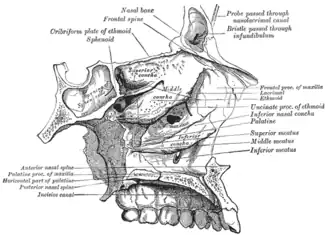

Lateral wall of nasal cavity, showing ethmoid bone in position.

Lateral wall of nasal cavity, showing ethmoid bone in position. -

Roof, floor, and lateral wall of left nasal cavity.

Roof, floor, and lateral wall of left nasal cavity. -